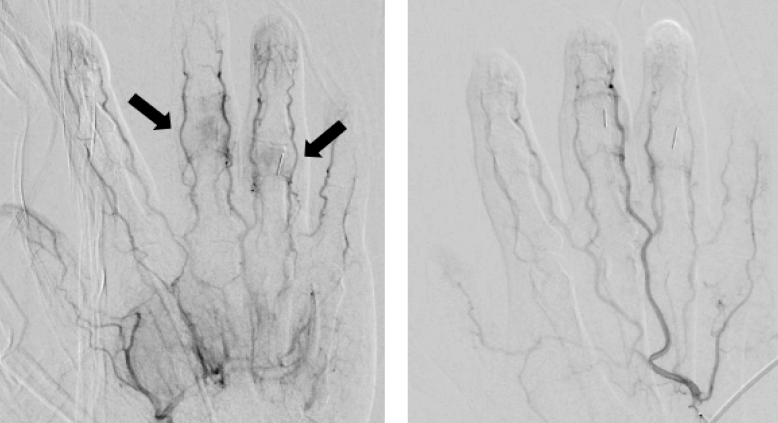

血管栓塞術於2013年由Okuno醫師提出[3],利用栓塞劑的結晶去阻塞因關節炎產生的新生血管,發現在新生血管[4]消失後,患者疼痛的狀況也跟著立即改善。後來便用於各處骨關節炎,在一篇文獻回顧中,發現在五十肩、網球肘/高爾夫球肘、腰痛、跳躍者膝、輕度變形的退化性關節炎、阿基里斯跟腱炎、足底筋膜炎、手指末端退化性關節炎、腕關節炎、薦髂關節炎、嚴重退化性膝關節炎等常見疾病都有效果[5],足見此種新式療法的泛用性。

我幫吳小姐使用了經超音波導引血管栓塞術治療手部的關節炎,在兩次的療程後,吳小姐就重拾了攝影的愛好,其他的患者也因這個療法重拾了跑步及運動的愛好,畢竟沒有了雙手與雙腳還真是萬萬不能。如果有相關需求,歡迎洽詢英爵診所,讓你關節重獲新生